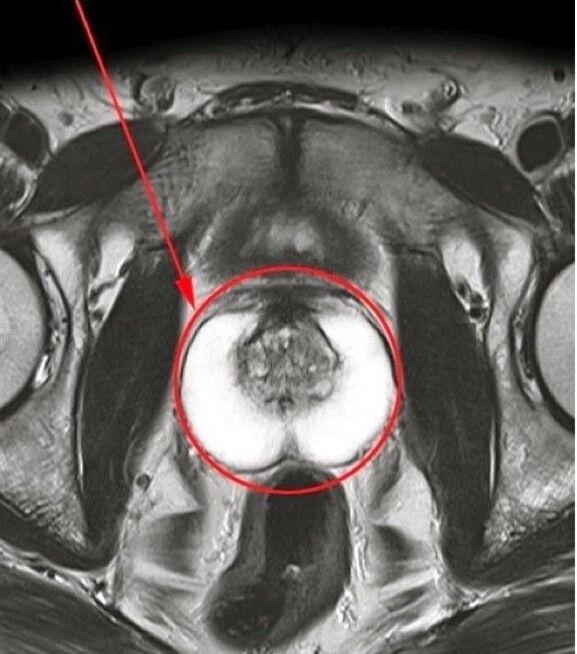

Bis elo, all d'Symptomer vum Prostatitis sinn verschwonnen, an ech fille mech komplett gesond. De magéiert fir d'Bikatt an seng natierlech Kanäfsehalen si lieweg Virdeeler.